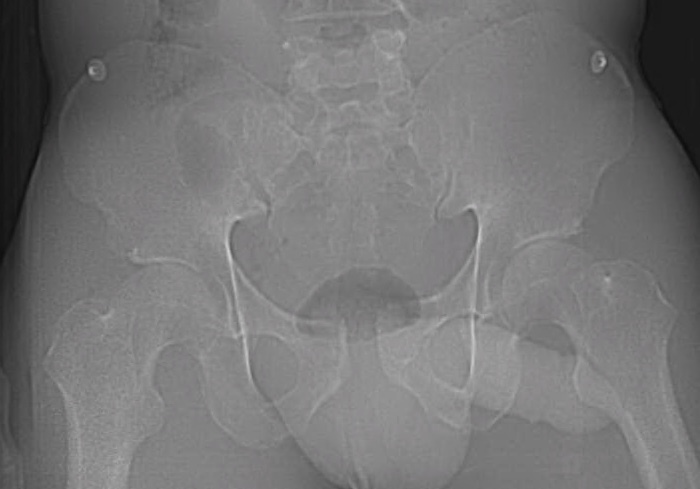

Chart review was undertaken to obtain basic demographic variables such as age, sex, smoking and diabetic history. Injury radiographs were reviewed to determine fracture type and Young-Burgess fracture classification. Preoperative and postoperative radiographs are demonstrated in figures 1A, 1B, 2A and 2B. Operative records were reviewed to determine which patients underwent screw removal and if any adverse intra-operative events occurred. Hospital charts and clinic charts were reviewed to document any postoperative complications and record pre and postoperative visual analog pain scales.